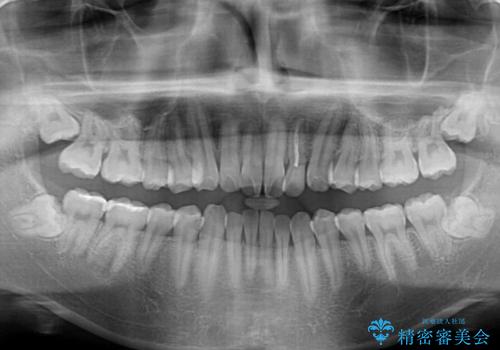

- 前歯のデコボコとクロスバイトを気にして来院された患者様です。

クロスバイトはありましたが、叢生の程度としては酷くなかったため、ワイヤー矯正でもマウスピース矯正でも、好きな方を選択していただきました。

気になっていたクロスバイトは速やかに改善され、1年間で治療を終えることができました。